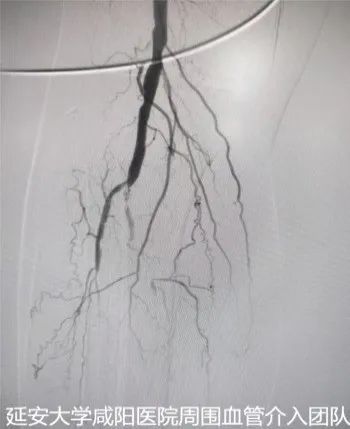

術前DSA